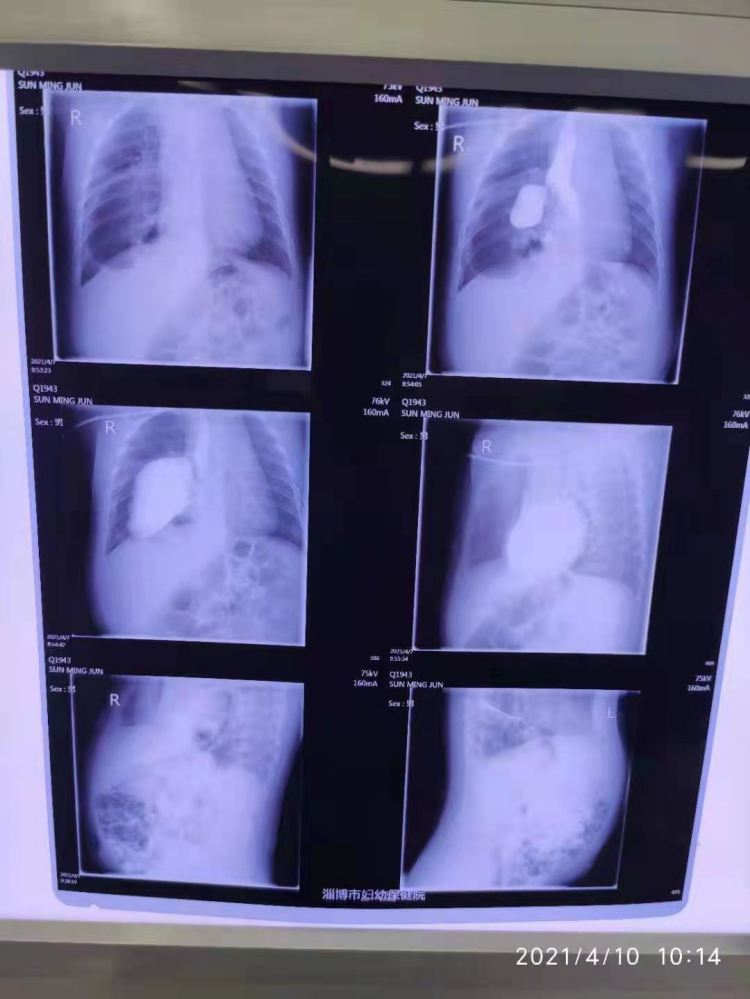

患儿年仅4个月大,因最近总是哭闹不安、呕吐,家属带其到淄博市妇幼保健院检查。“来院就诊时孩子已出现呼吸喘憋、恶心呕吐的症状。通过完善检查,我们发现孩子有先天性食管裂孔疝,其食胃肠道等腹腔脏器通过膈肌裂开的疝口,疝入了胸腔。”淄博市妇幼保健院小儿外科主任张正茂介绍,儿童先天性食管裂孔疝是指胃通过异常宽大的食管裂孔突入到胸腔内形成的疝,可伴或不伴有疝囊,病因多为先天性膈裂孔发育不全。

如果患儿不及时救治,可导致呼吸困难、呕吐、不能进食,严重时会因呼吸困难危及生命。以往这类巨大疝囊的食管裂孔手术 ,都需要开腹手术。术后患儿留下了巨大的手术疤痕。随着儿童腹腔镜技术的不断发展,当先腹腔镜下食管裂孔疝修补和胃底折叠术已成为外科治疗儿童食管裂孔疝的主要方法。4月10日上午,对患儿的腹腔镜下食管裂孔疝手术在家属期盼下展开,在医护人员2个半小时的协作努力下,整个手术顺利完成。